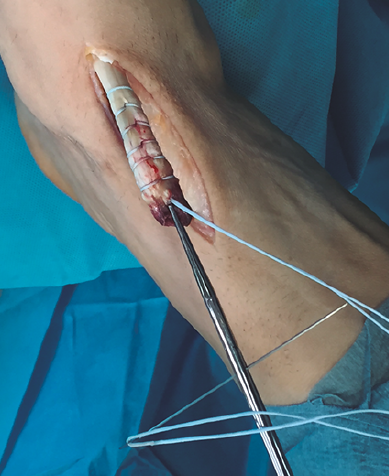

Figura 3. Sutura del tendón tibial anterior con hilo no absorbible.

Se realiza una disección y liberación del TA, resecando la porción distal más degenerada del tendón en forma de punta para introducirlo a través del túnel óseo con mayor facilidad y se sutura con hilo no absorbible (Figura 3), que después pasaremos a través de los orificios de la placa metálica de anclaje extracortical (de dimensiones de 4 × 12 mm).